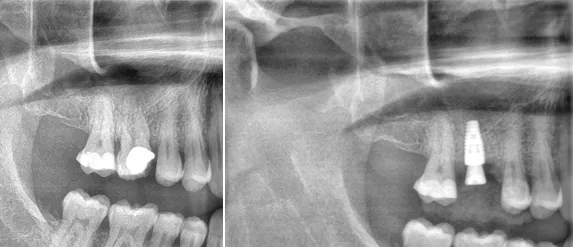

Omedelbar implantatplacering efter tandextraktion – effektiv behandling med bevarad vävnad och förkortad läkningstid På Käkkirurgiskt Centrum Skåne arbetar vi med moderna och beprövade behandlingsmetoder inom tandimplantatkirurgi. En av de tekniker som blivit allt mer etablerad i både vetenskap och klinisk praxis är omedelbar implantatplacering, det vill säga att ett tandimplantat sätts in direkt efter att en tand […]

Vid omedelbar implantatbehandling – där implantatet placeras direkt efter att tanden dragits ut – är det avgörande att skapa en så ren och stabil miljö som möjligt för implantatet. Speciellt vid tidigare infektion i området måste allt infekterat material avlägsnas.

All granulationsvävnad och infekterad vävnad måste tas bort mekaniskt från både ben och mjukvävnad. Detta minskar risken för komplikationer som periimplantit, benförlust och implantatförlust.

Efter debridering används ett flerskiktsprotokoll med olika antibakteriella lösningar (t.ex. klorhexidin, natriumhypoklorit och EDTA) för att reducera bakterienivåerna maximalt.

???? En systematisk översikt i Journal of Periodontology visar att implantat i infekterade områden kan lyckas – om infektionskontrollen är noggrann och vävnaden hanteras korrekt.